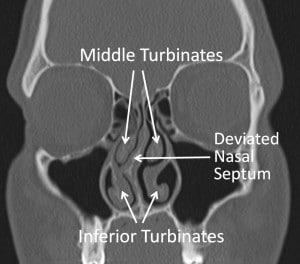

The inside of the nose is a complex area with intricate anatomy (structure) and physiology (function). Our nose is important for breathing, smell and taste, and sinus function. One important part is the nasal septum which is the wall separating the two nostrils and nasal passages. The septum is made up of cartilage and bone covered by mucosa. This thin wall made of cartilage is ideally located almost equally between your two nostrils which results in symmetric size of the nasal passages. However, some people have a deviated septum that they were either born with or developed somewhere along the way. It’s not necessary to have a perfectly straight septum; very few people do. A slightly off-center septum may not cause any problems, but a significantly deviated septum often causes noticeable symptoms and can be corrected through a procedure known as nasal septoplasty. In some cases a person with a mildly deviated septum has symptoms only when they have a cold or upper respiratory infection. In these patients the infection triggers increased nasal inflammation that temporarily amplifies any mild airflow problems related to the deviated septum. Once the cold resolves and the inflammation subsides, the symptoms usually resolve too.

If these symptoms occur, surgery to correct the anatomic problem may be beneficial. Your physician may find that symptoms are stemming not only from a deviated septum, but also from swollen turbinates along the walls of your nasal passage.

Turbinates are shelves of bone that are covered with special mucosa. The mucosa can swell several times normal size. This can cause air flow to be blocked leading to the symptoms described above.